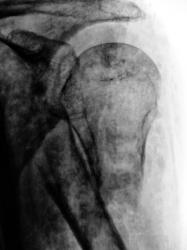

Катенёв Валенти... Дата публикации 29.07.2009, 20:45 Травма. Пациент направлен врачом хирургом в рентгеновский кабинет для рентгенографии лучезапястного сустава и дистальной трети костей предплечья. Чт, 30/07/2009 - 19:03 #1 Vega Не на сайте Был на сайте: 1 неделя 18 часов назад Зарегистрирован: 22.01.2009 - 19:16 Публикации: 1087 Бывает... Пт, 31/07/2009 - 21:54 #2 OPEXOB Не на сайте Был на сайте: 9 лет 12 месяцев назад Зарегистрирован: 26.07.2008 - 10:02 Публикации: 280 Т.е никакая. На операционный стол и металлоостеосинтез. Пт, 14/08/2009 - 21:27 #3 Катенёв Валенти... Не на сайте Был на сайте: 7 лет 1 месяц назад Зарегистрирован: 22.03.2008 - 22:15 Публикации: 54876 Пациент после репозиции и наложения "гипсовой повязки", направлен на контрольную рентгенографию.

Пациент после репозиции и наложения "гипсовой повязки", направлен на контрольную рентгенографию.